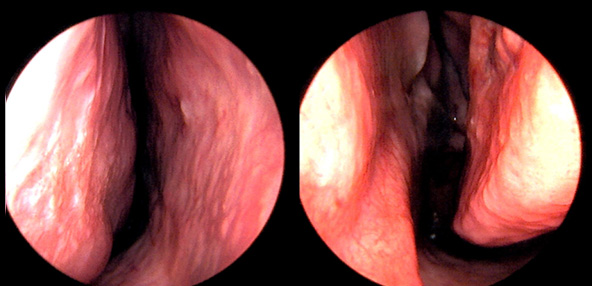

본 사진은 의료기관에서 진료를 본 환자이고, 전후 사진 인물이 동일인이며,동일조건에서 촬영이 되었습니다.